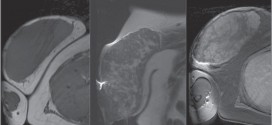

Leer MásHIPERPLASIA MALIGNA DE MAMA

La hiperplasia maligna de mama. La característica básica de la malignidad es una anormalidad de las células, transmitida a las células hijas, a saber, que se manifiesta por la posible reducción del control del crecimiento y la función celular, conduciendo a una serie de fenómenos adversos en el huésped, a través de un crecimiento masivo, invasión de los tejidos vecinos …